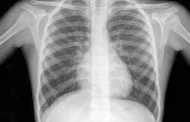

بلاحدود bilahodoud.ma على غرار دول العالم، تخلد وزارة الصحة والحماية الاجتماعية اليوم العالمي لمحاربة داء السل، الذي يُنظم هذه السنة تحت شعار: “السل يتجاوز الرئتين: لنعزز الوعي بالأشكال خارج... اقرأ المزيد